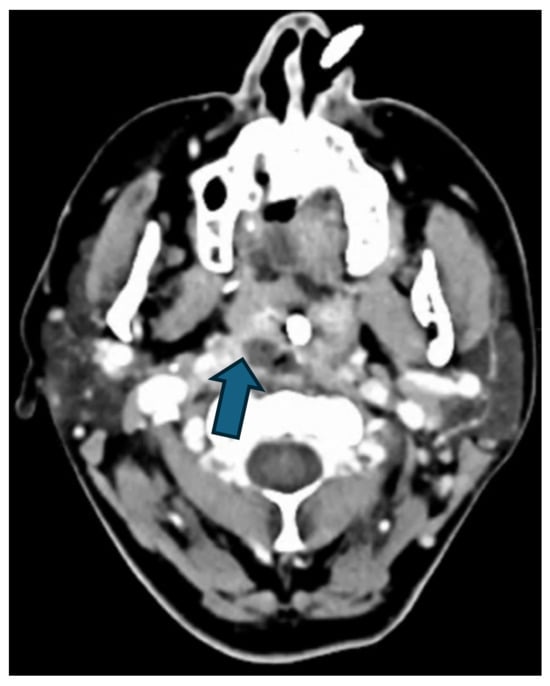

Regarding the source of infection, 77% (n = 17) of patients had DNM originating from oropharyngeal infections, while 23% (n = 5) had odontogenic sources. All patients underwent CT scans for the primary diagnosis (Figure 2 and Figure 3), and if required, serial CTs were performed to monitor the disease’s progression.

Figure 2. Hypodense formation (blue arrow) with peripheral contrast enhancement in the right retropharyngeal region, beginning paramedian caudal to the right pharyngeal tonsil/at the level of the C2 vertebral body, with gas inclusion in a patient with retrotonsillar abscess.

Figure 3. CT findings of the same patient presented in Figure 2, demonstrating the progression of DNM. (a) Gas inclusions (blue arrow) extending along the platysma muscle and thyroid gland into the anterior mediastinum; (b) Gas inclusions (blue arrow) posterior to the manubrium sterni with right sided pleural effusion.